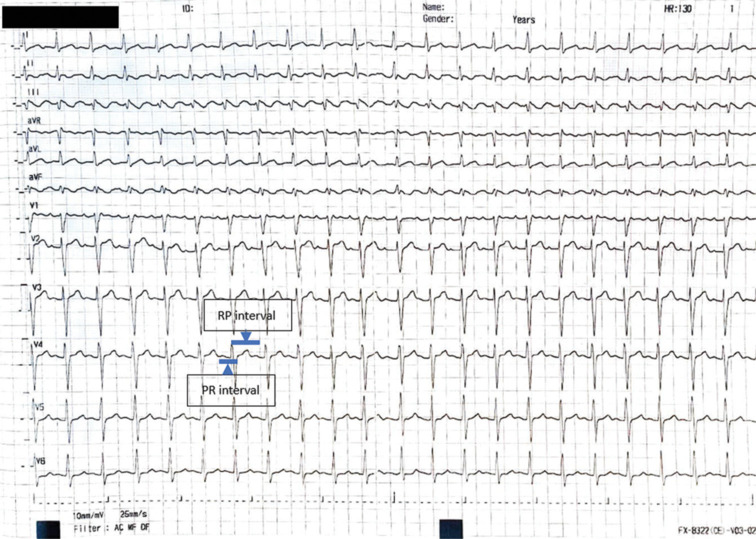

背景:房性心动过速的诊断有时可能具有挑战性。利用超声心动图(主要是经食管超声心动图)评估左心耳(LAA)的多普勒血流模式,是建立心房速性心律失常诊断的有价值的工具,特别是在诊断尚不明确的情况下。结果:该方法简便有效,但在临床实践中应用不足。结论:本文旨在强调结合LAA血流与心电图诊断复杂病例心房速性心律失常的有效性,特别是心房扑动,并鼓励医生采用这种方法更好地识别心房速性心律失常复发和LAA血栓形成的风险患者。

Background: The diagnosis of atrial tachyarrhythmias might be challenging at times. Assessing Doppler flow patterns of the left atrial appendage (LAA) using echocardiography, mainly transesophageal echocardiography, represents a valuable tool for establishing the diagnosis of atrial tachyarrhythmias, especially when the diagnosis remains unclear.

Result: Despite its effectiveness and simplicity, this technique is often underused in routine clinical practice.

Conclusion: This paper aims to underscore the effectiveness of using LAA flow in conjunction with electrocardiograms for diagnosing atrial tachyarrhythmias in complex cases, particularly atrial flutter, and to encourage physicians to adopt this approach to better identify patients at risk for the recurrence of atrial tachyarrhythmias and LAA thrombus formation.